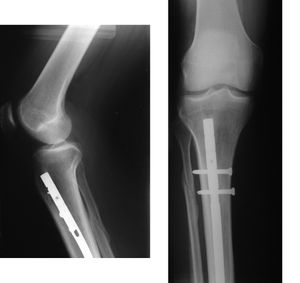

; 내고정

: 수술을 통해 금속판, 와이어, 핀 등의 고정 도구를 사용하여 뼈를 접합하는 방법.

; 경피적 강선 고정

: 키르시너 와이어 등을 사용하여 X선 투시 하에 피부 밖에서 뼈를 꽂아 고정한다(오른쪽 상단 그림 참조).

: 키르시너 와이어 등을 사용하여 X선 투시 하에 피부 밖에서 뼈를 꽂아 고정한다.